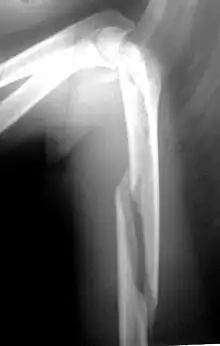

Fratura de úmero

Fratura de úmero se refere a ruptura do úmero, o maior osso do braço. As fraturas proximais são próximas ao ombro (25% dos casos), mediais na diáfise (60% dos casos) e as distais ocorrem próximo ao cotovelo (15% dos casos). Essa classificação pode ser subdividida, com base na extensão da fratura e nas partes específicas do úmero. [1]

Quando há suspeita clínica são solicitadas duas radiografias, frente e perfil ou duas oblíquas, dependendo do local afetado. Tomografia computadorizada pode dar mais informações sobre a fratura.[8]